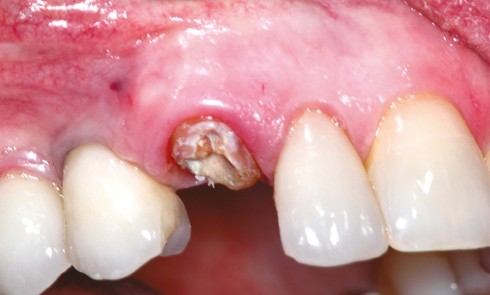

Article réservé à nos abonnés Extraction implantation immédiate et choix raisonné du matériau de comblement

Lorsqu’un patient est atteint d’une fracture radiculaire ou d’une infection endodontique, parodontale ou endo-parodontale, ou qu’il présente une rhizalyse terminale...